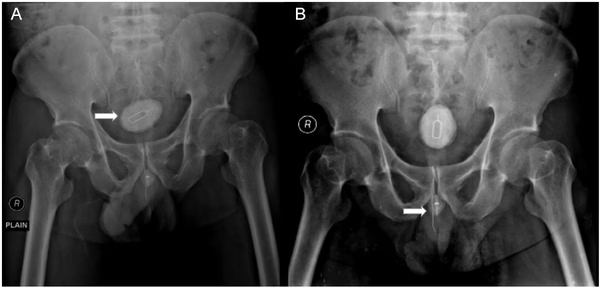

Homem é submetido a cirurgia para retirar chip, cabo elétrico e elástico introduzidos no pênis 12/04/2024 as 17:57 Receba notícias em seu WhatsApp Participe da nossa comunidade